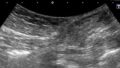

骨盤静脈疾患のエコー診断

静脈学会HPに掲載されている骨盤静脈疾患のSVP(症状-静脈瘤-病態生理)分類を元に分類方法やエコー操作方法を説明して下さいました。

エコーでは仰臥位と立位で逆流評価をするそうです。症例やレポートも提示して下さり、きれいなエコー画像も拝見できて勉強になりました。